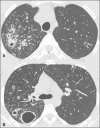

Objective: To describe the relationship between coronavirus disease 2019 (COVID-19) and pulmonary tuberculosis during the current pandemic, as well as to describe the main computed tomography (CT) findings in patients suffering from both diseases simultaneously.

Materials and methods: This was a retrospective, cross-sectional observational study of the chest CT scans of 360 patients with COVID-19, as confirmed by RT-PCR.

Results: In four (1.1%) of the patients, changes suggestive of COVID-19 and tuberculosis were observed on the initial CT scan of the chest. On chest CT scans performed for the follow-up of COVID-19, cavitary lesions with bronchogenic spread were observed in two of the four patients, whereas alterations consistent with the progression of fibrous scarring related to previous tuberculosis were observed in the two other patients. The diagnosis of tuberculosis was confirmed by the isolation of Mycobacterium tuberculosis.

Conclusion: Albeit rare, concomitant COVID-19 and tuberculosis can be suggested on the basis of the CT aspects. Radiologists should be aware of this possibility, because initial studies indicate that mortality rates are higher in patients suffering from both diseases simultaneously.